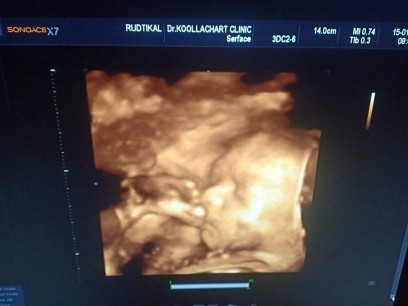

ซาวด์ตอน27วีคค่ะ ปัจจุบัน36วีค ลูกชาย